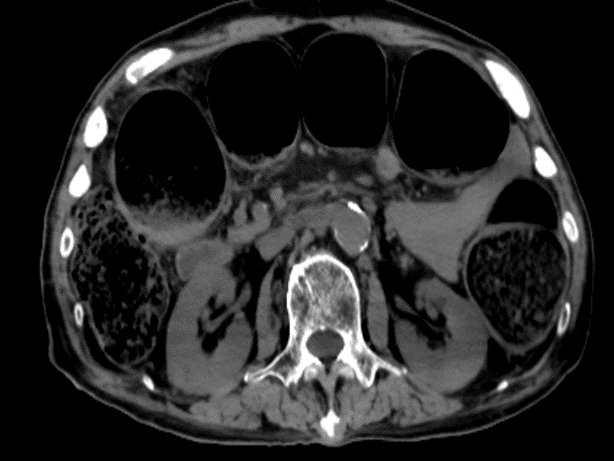

"患者意识不清,双侧瞳孔不等大!"接诊医生周淑清的呼喊打破了夜的宁静。急诊团队立即启动绿色通道,15分钟内完成头胸腹CT检查。

结果令人揪心:急性脑出血合并乙状结肠癌完全性肠梗阻,肠镜结果乙状结肠肠腔完全堵死。"就像两把刀同时架在脖子上。"患者的主治医师邵庆亮这样形容当时的危急情况。